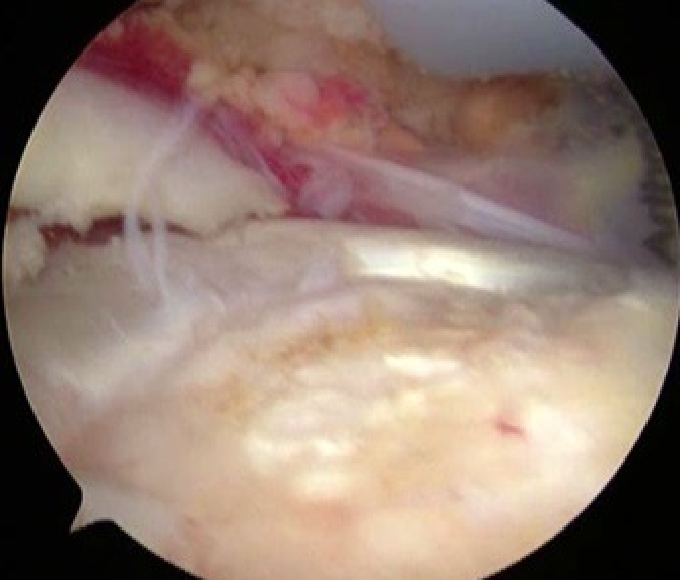

③腱板縫合

U字型の中断裂

上腕骨頭(大結節Footprint)が露出してしまっている。

④関節唇修復

必要に応じて、上腕骨頭を肩甲骨関節窩に安定させる関節唇を修復します。